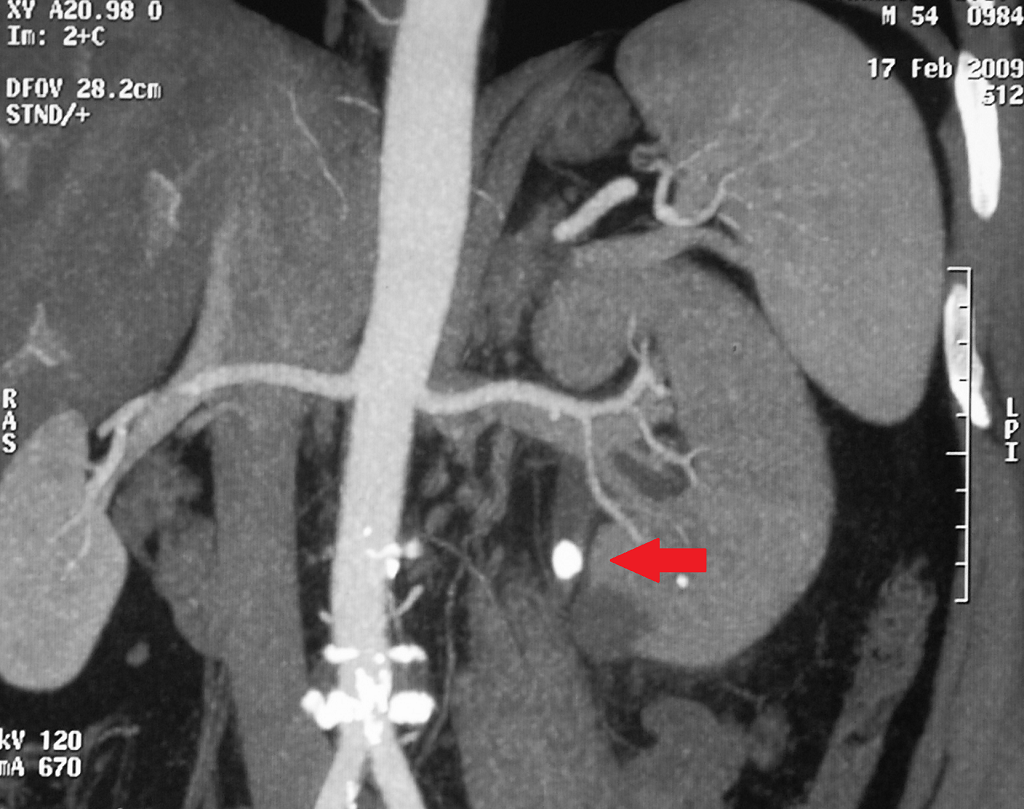

Изображения КТ конкрементов мочевого пузыря